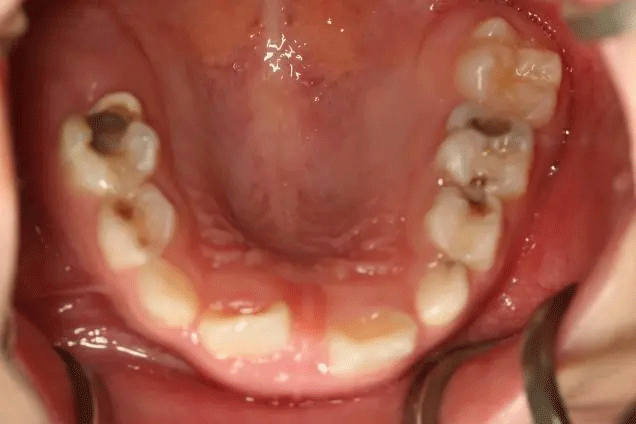

很多家長對乳牙蛀牙不以為然

孩子1歲開始已經(jīng)出現(xiàn)齲齒

但是媽媽2年后才帶孩子就診

這時,孩子已經(jīng)斷斷續(xù)續(xù)疼了3年

在門診中發(fā)現(xiàn)

來口腔科檢查的孩子

有些牙齒都已經(jīng)爛得很嚴重了

甚至牙齒幾乎都爛光僅剩下牙根

孩子不喊疼,家長很少會帶來看牙